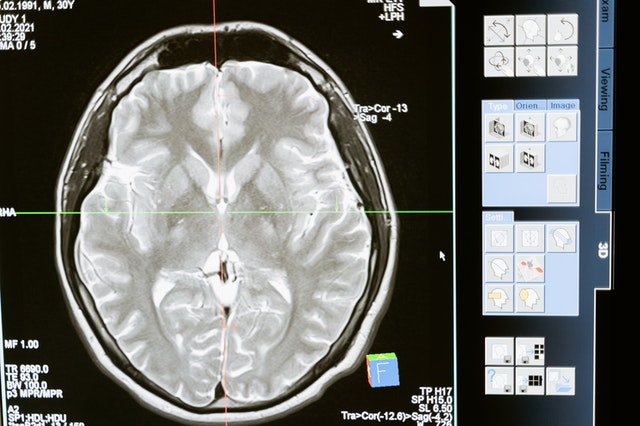

The study found that the brain’s outer surface or cortex has been shrinking for thousands of years. This is significant because the cortex is responsible for complex tasks such as memory, language and reasoning.

This study suggests that the answer may be both. It’s clear that the brain is responsible for complex tasks such as memory, language and reasoning.